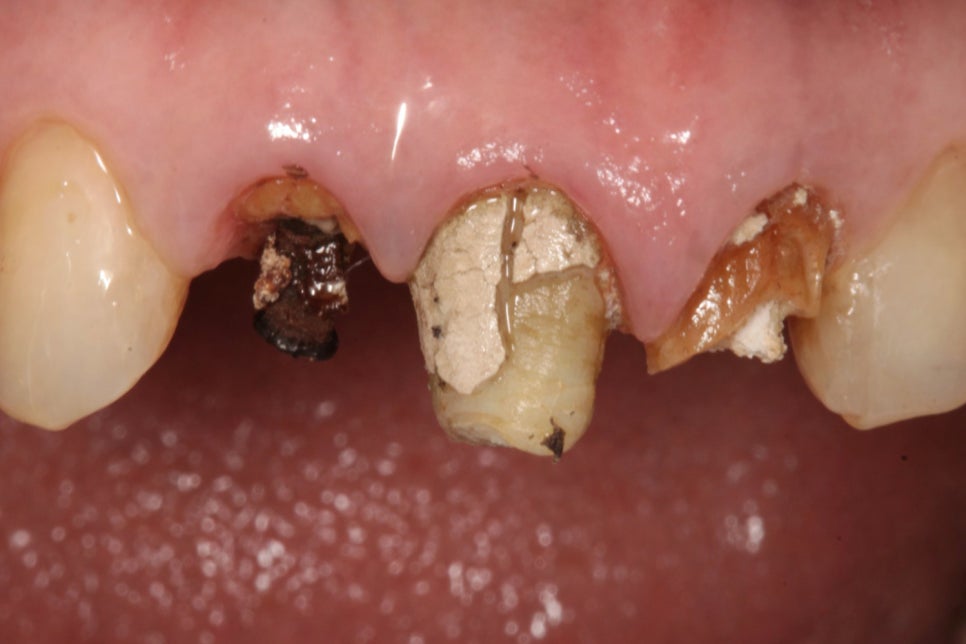

2차 우식은 크라운 아래에서 진행되기 때문에

초기에는 겉으로 드러나는 변화가 없을 수 있습니다.

또한 보철 아래에서 발생한 충치는

외부 공기와 접촉하지 않기 때문에

비교적 습하고 밀폐된 환경에서

빠르게 진행될 수 있습니다.

그 결과 치질이 약해지고

결국 치수까지 감염되거나

치근단 염증으로 이어질 수 있으며

재수복만으로는 해결이 어려워집니다.

경우에 따라서는 자연치를 보존하지 못하고

발치로도 이어질 수 있으며